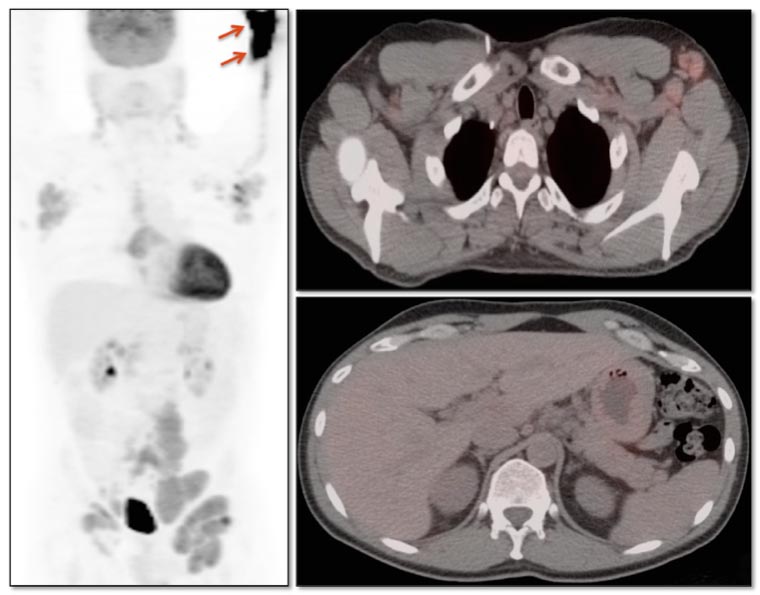

Extravasation:

FDG is injected intravenously. As many oncology patients have challenging venous access, partial extravasation of FDG during injection is not uncommon.

This extravasated FDG can cause false positive uptake in adjacent nodes and vessels (discussed here). Additionally, the resulting decrease in available FDG for circulation in the body (and absorption into tumors) can lead to false negative results (the “Sponge Effect”, discussed here). [FIG. 5] [FIG. 6]